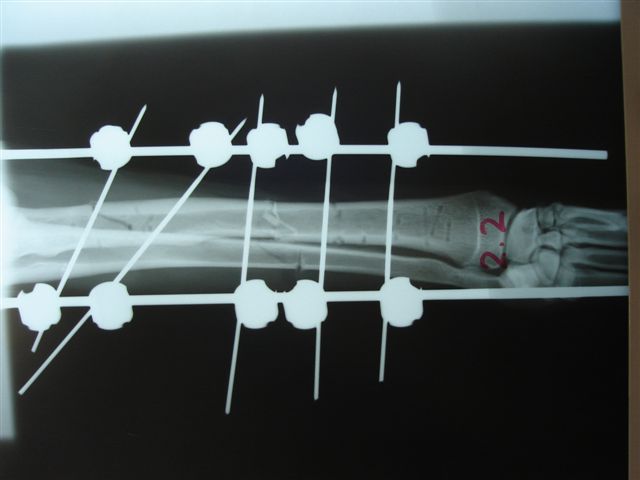

Fijación Externa en IVOT

Fijación Externa

IX CURSO BASICO DE FIJACION EXTERNA.

Casos prácticos alumnos.